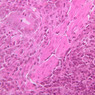

Here's a little histopathology: Observe slide A-40 (H&E [2.5x, 10x, 20x, 40x]). In this slide the corpses of red blood cells appear brown and can be seen littered throughout. These residual RBCs are referred to as hemosiderin. Slide A-39 (H&E [2.5x, 10x, 20x, 40x]) was prepared from a patient undergoing chemotherapy. How does the white pulp in this slide differ from the normal spleen, slide A-38?